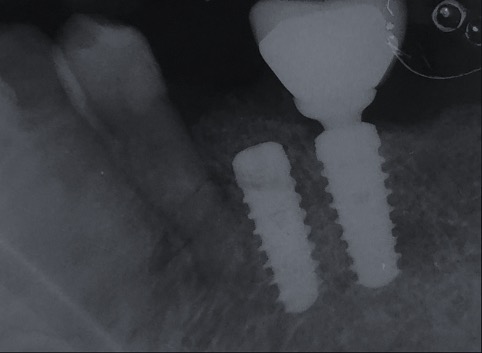

Un impianto dentale o fixture è un corpo in titanio, totalmente biocompatibile, che viene posizionato nella mascella o mandibola con lo scopo di sostituire la radice di un dente naturale perso. Su di esso viene successivamente o immediatamente quando possibile (carico immediato) fissata la protesi ovvero la corona del dente restituendo funzione ed estetica.

In alcuni casi è possibile non incidere la gengiva ed inserire un impianto con tecnica Flapless, questo rende la fase post-operatoria più confortevole per il paziente riducendo gonfiori e fastidi.

Il carico immediato è possibile quando l’osso ha una qualità tale da dare una stabilità meccanica immediatamente adeguata all’impianto.